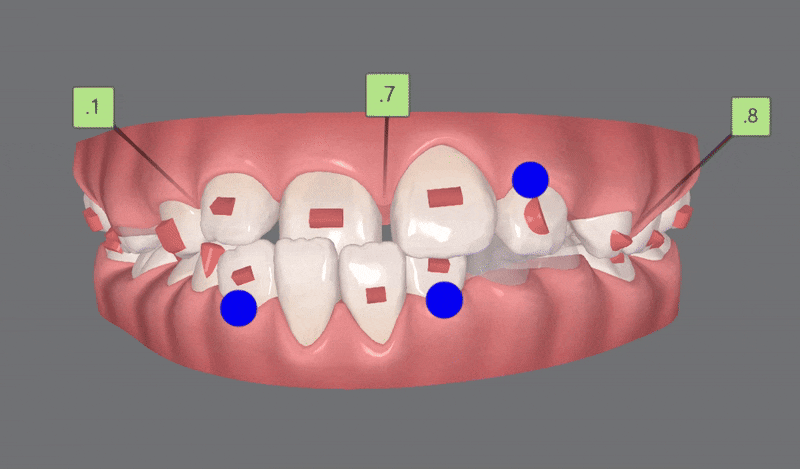

2nd Clincheck(21개)

두번째 클린체크에서는

21개의 장치로 진행해드렸는데요.

기존 어태치먼트에 추가로 어태치를 부착해

치아이동을 원활하게 도와주었습니다.